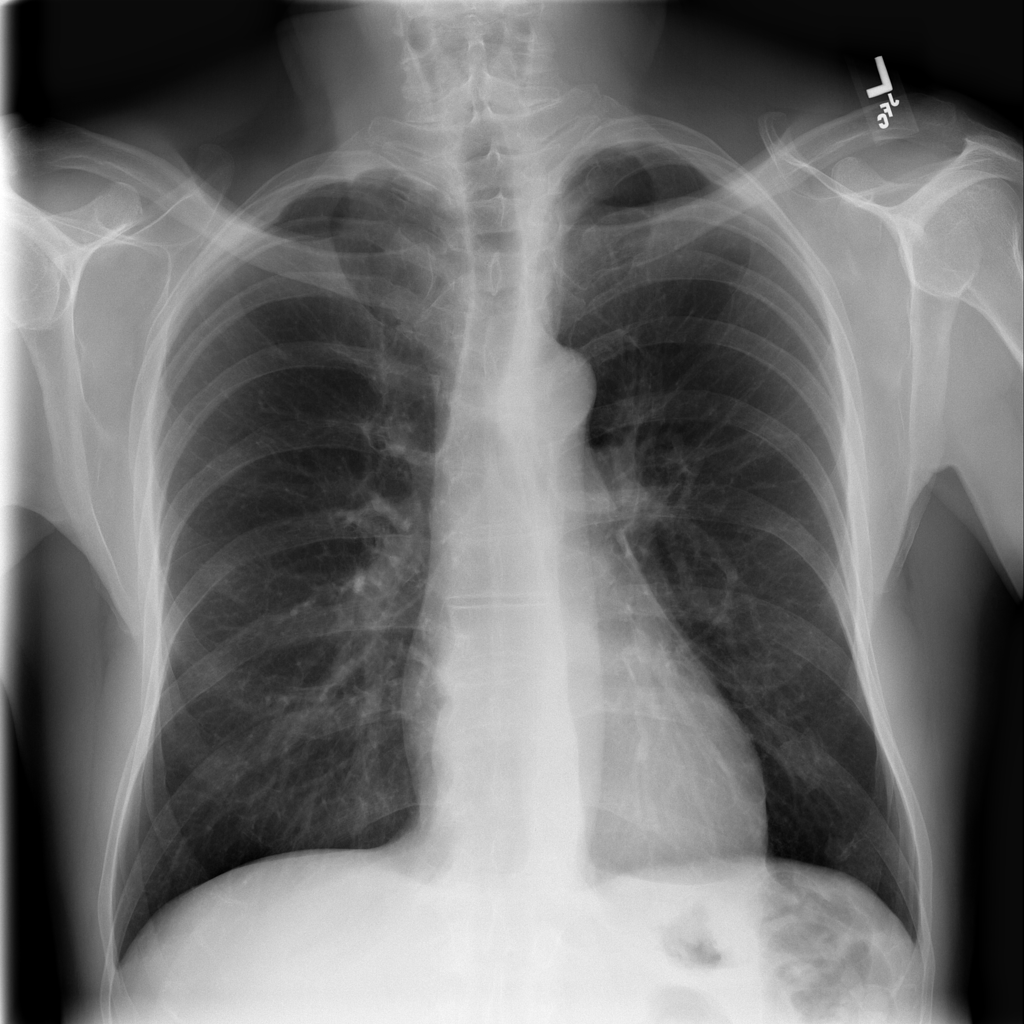

PAT-894B · IMG-000Emphysema

PAT-894B · IMG-000

PA